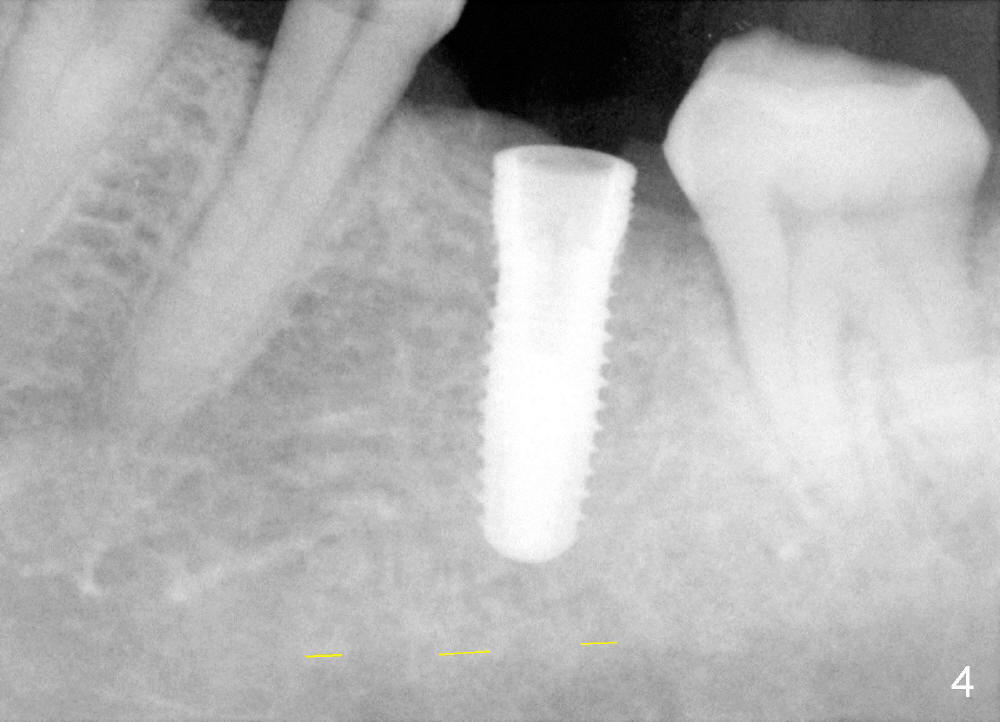

Fig.2 shows calculus in the mesial sulcus of #18 preop. After calculus removal, a 10 mm paralleling pin is inserted (Fig.3); it appears that the apical end should be moved mesially (arrow). Finally a 5x14 mm implant is placed as planned (Fig.4).